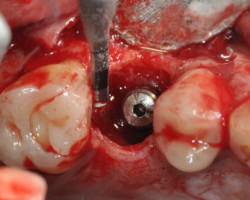

- Phase correctrice : créer des conditions compatibles avec la maintenance. (chirurgie résectrice, implantoplastie, correction prothétique)

- Phase réparatrice: Réduire la profondeur de poche et réparer les tissus détruits.

Techniques résectrices

Techniques régénératrices

Techniques combinées